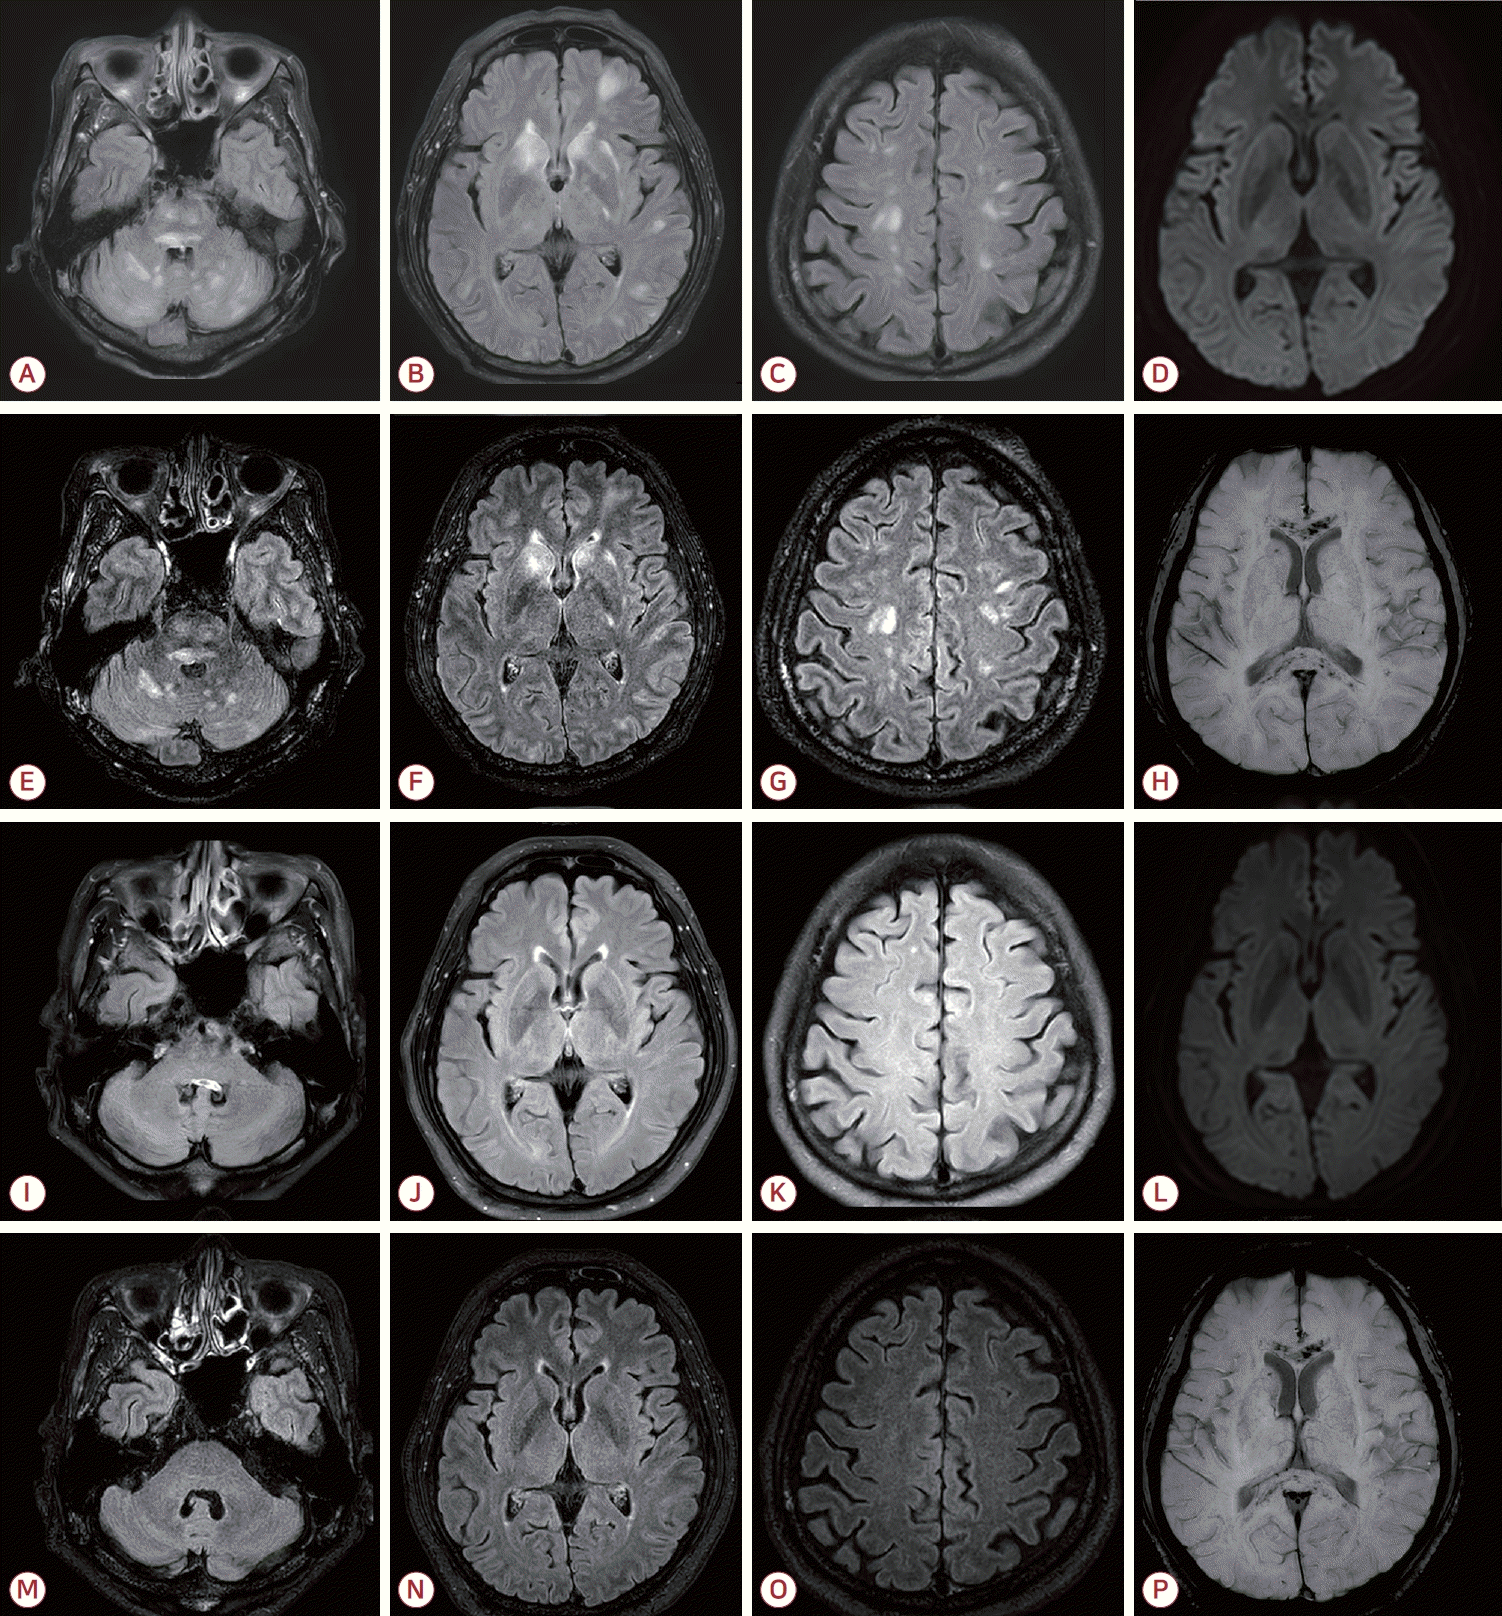

Initial brain MRI demonstrated multiple T2/FLAIR hyperintense lesions involving the brainstem, cerebellum, deep gray matter, cerebral cortex, and subcortical white matter (A-C). Diffusion-weighted imaging (D) showed no diffusion restriction. Contrast-enhanced FLAIR images revealed multiple tiny enhancing nodules, predominantly in the brainstem and cerebellum, and to a lesser extent in the cerebral hemispheres (E-G). SWI showed diffuse microbleeds in the corpus callosum and subcortical white matter (H). On follow-up MRI after 4 months, most hyperintense lesions had resolved (I-K, M-O). Diffusion-weighted imaging again showed no diffusion restriction (L). Contrast- enhanced FLAIR demonstrated interval disappearance of the previously noted tiny enhancing nodules (M-O). However, diffuse microbleeds persisted in the corpus callosum and subcortical regions (P). MRI; magnetic resonance imaging, FLAIR; fluid-attenuated inversion recovery, SWI; susceptibility-weighted imaging.